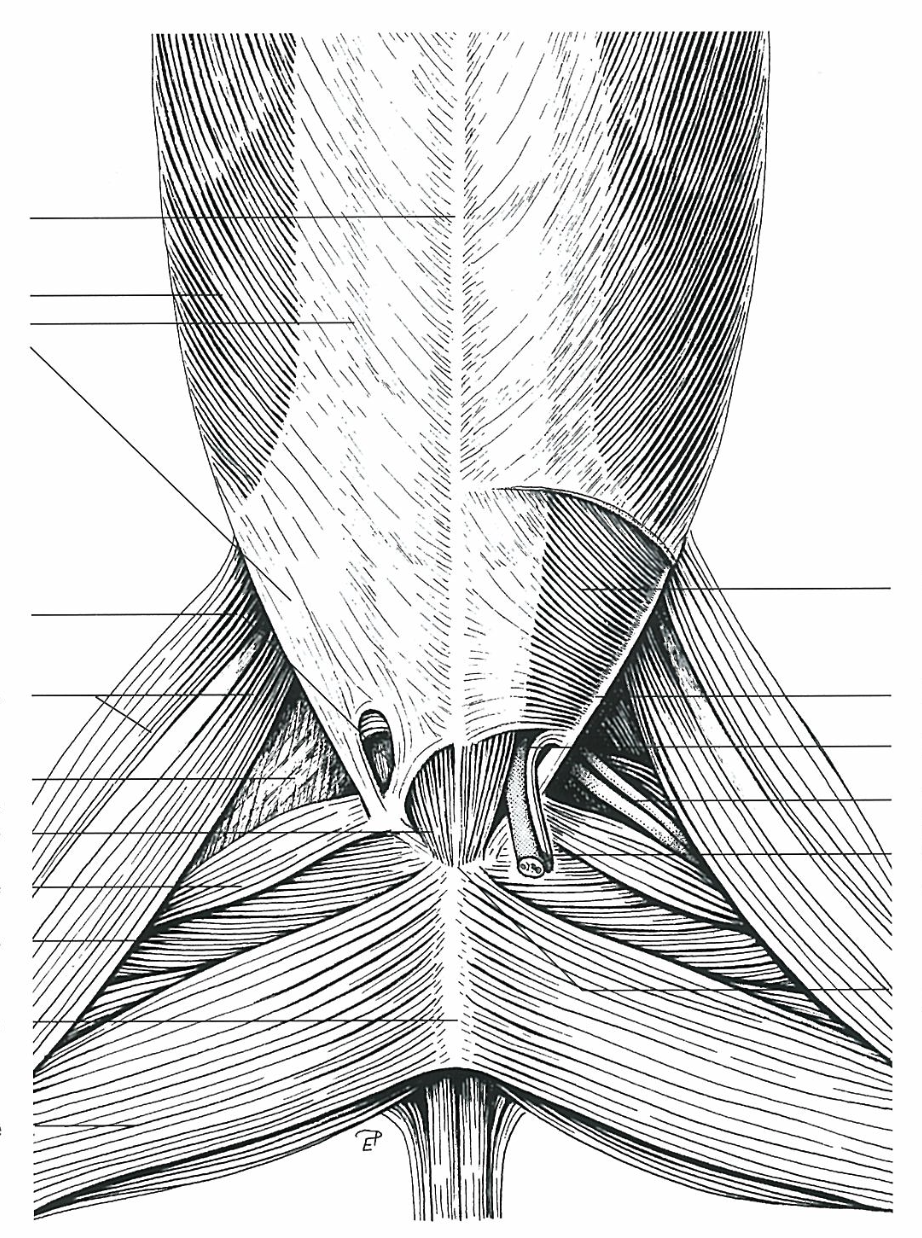

**Anulus inguinalis superficialis**

26

**M. obliquus internus abdominis**

27

**M. obliquus externus abdominis**

28

**Tunica vaginalis**

29

**Proc. vaginalis**

30

**Lig. teres uteri**